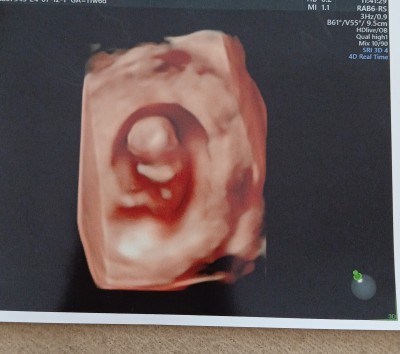

Cinsiyet tahmini :)

Kizlar merhaba insallah soruyu dogru yerde sormusumdur

2 gun once doktor cinsiyet tahmininde bulundu ama.net bse solemedi 1 ay sonra netlesir dedi. Suan 12+1. Burda cok okudum sonrada farkli cikio diye. Smdi diceksiniz biz doktordan iyimi bilcez. Haklisiniz ama insan merak ediyor işte

Erkek doğdu içime. Sağ Salim dolsun inşallah

Ben ozele 12+3gittigimde doktor kiz gibi geliyor dedi haftaya gel dedi kontrole 13+4gittim doktor erkek dedi yani degisiyor o haftalarda 19 hadtalikkken gittigimdede net erkek dedi

Ben kız diyorum oğlumun 12 haftalık ultrasonuna benzemiyor